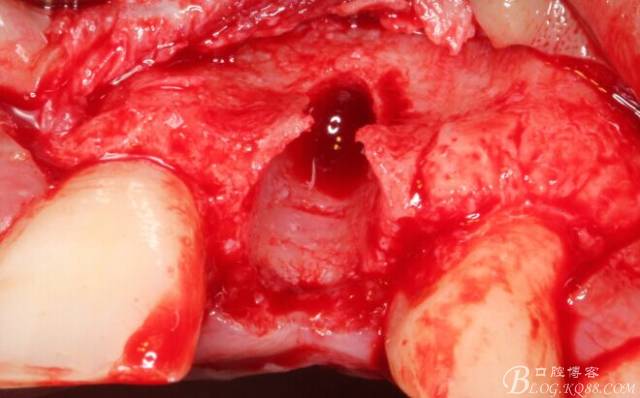

徹底搔刮拔牙窩,偏腭側(cè)備洞

順利植入植體,扭力30N。三壁骨,感覺美美的